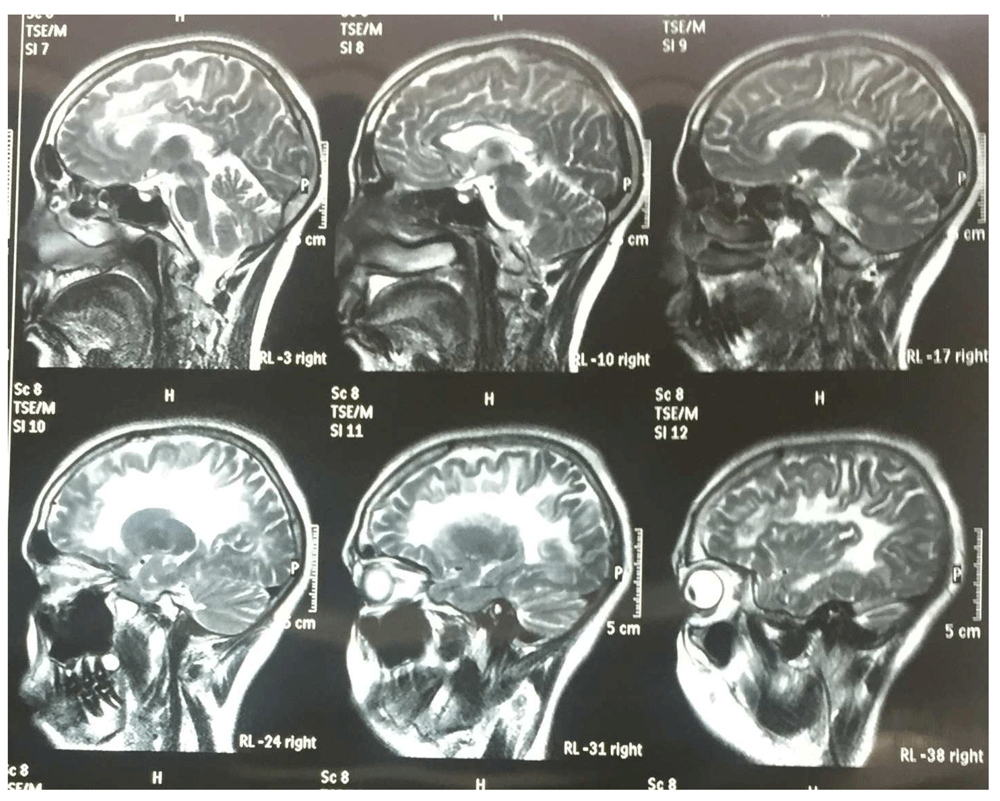

Her MRI brain scan was remarkable for diffuse leukodystrophy (Figure 1 and Figure 2). Her hormonal assays were consistent with premature menopause (Table 1). An ultrasound of her abdomen and pelvis was remarkable for small ovaries and uterus. Her lumbar puncture results were normal and there were no oligoclonal bands in her cerebrospinal fluid (CSF). She underwent genetic tests including sequence analysis and polymerase chain reaction (PCR), which demonstrated a point mutation in the EIF2B4 gene. Thus, she was diagnosed as a second case of VWM from the same family of 12 siblings and 2 parents. None of the family members were screened due to affordability issues.

The diagnostic workup includes MR imaging of the central nervous system which demonstrates diffuse and cystic degenerative loss of the deep cortical white matter and U-fibers. The grey matter is preserved3,5,6. This is due to a mutation in EIF2B which causes impairment of protein synthesis under conditions of cellular stress like infection, trauma, intense emotions and surgery. The genetic tests confirm the diagnosis6. Those females who live into adulthood develop ovarian failure2,4,6. Interestingly, according to our literature search, primary testicular failure has not been described in any reported case of affected males .